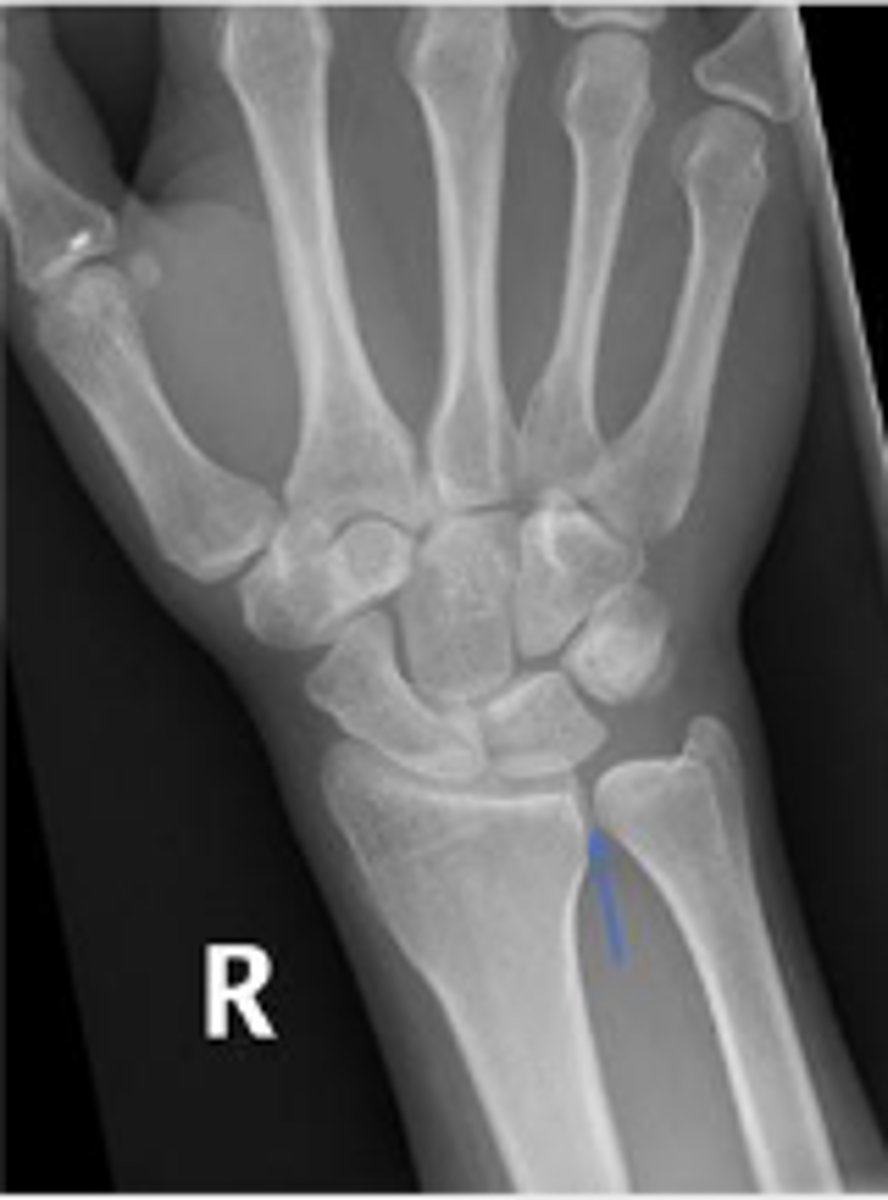

PA right wrist

Right scaphoid

What is the arrow pointing to?